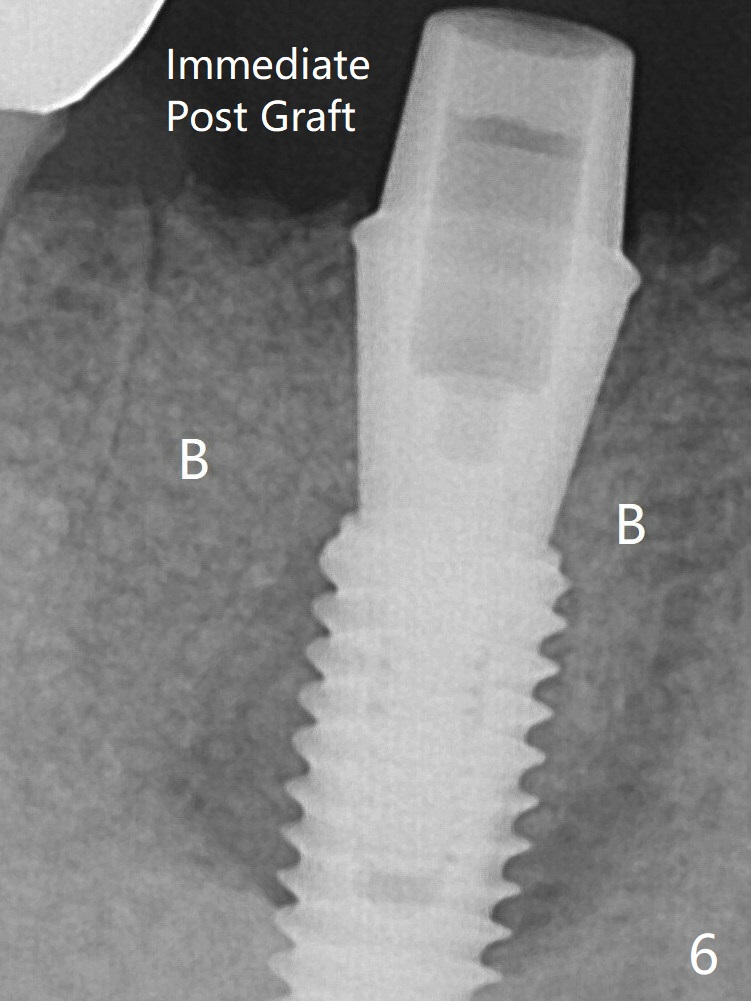

Mixture of cortical bone (125μm – 850μm) and cortical/cancellous bone (.5-1 mm) with PRF (sticky bone, B in Fig.6). There is not enough bone coronal to the implant plateau 2 months post graft (Fig.12). Three months later, bone graft will be re-placed possibly with uncover.